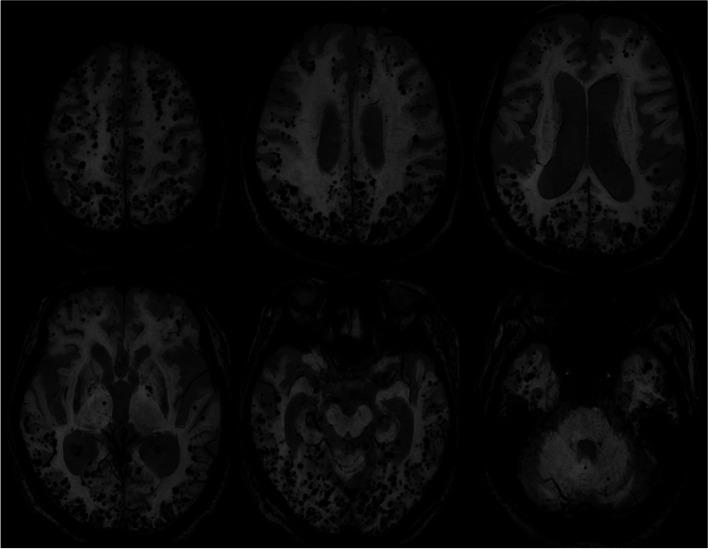

An 83-year-old woman diagnosed with hepatitis B virus-related liver cirrhosis 40 years before was referred to our neurology clinic for progressive disorientation of time and place, personality changes, and confusion with somnolence over 2 weeks. Based on the laboratory, neuroimaging, and electrophysiological findings, we diagnosed the patient with hepatic encephalopathy, and her symptoms recovered within 12 h after proper medical management. Brain MRI showed innumerable CMBs in the bilateral frontal, parietal, temporal, and occipital lobes. Since the distribution of CMBs in the patient was mainly corticosubcortical and predominantly in the posterior cortical regions, and the apolipoprotein E genotype was ε4/ε4, we speculated that CAA and hepatic encephalopathy coexisted in this patient.

一名 83 岁女性,40 年前被诊断为乙型肝炎病毒相关肝硬化,因 2 周来逐渐出现时间和地点定向障碍、人格改变和伴嗜睡的意识混乱,被转至我院神经内科就诊。根据实验室、神经影像学和电生理学检查结果,我们诊断该患者为肝性脑病,经适当的药物治疗后,其症状在 12 小时内得到缓解。脑 MRI 显示双侧额、顶、颞和枕叶存在无数 CMB。由于该患者的 CMB 分布主要为皮质下和皮质后区为主,载脂蛋白 E 基因型为 ε4/ε4,我们推测该患者同时存在 CAA 和肝性脑病。